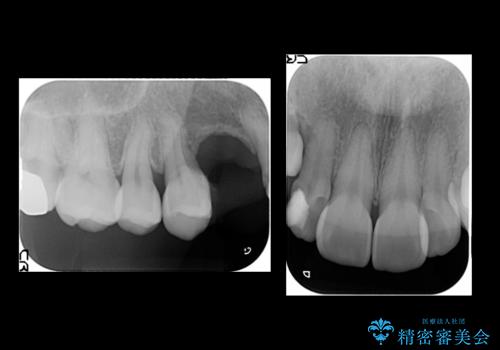

- 右上の歯はもともとなかったが、ブリッジにするのが嫌でプラスチックの歯を応急的に接着剤でつけていたのがとれてしまったとのことでした。

接着剤で留めてある周りが、虫歯になってしまっていました。

しっかり虫歯を取ったうえで、清掃性の高いブリッジにしていくことをおすすめしました。

右上④3②①ブリッジの設計としました。

右上2番単独の支台歯では不足のため、右上12とも支台歯にしています。